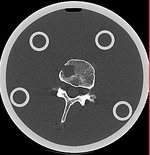

registered (after flipping axis and cropping volume) registered